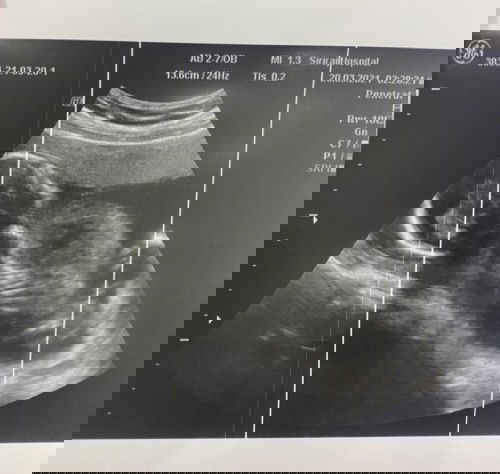

พุงใหญ่จนอาจารย์หมออดขำไม่ได้ น้ำหนักแม่ก่อนท้อง 60 กิโล ตอนนี้ 4 เดือนน้ำหนัก 61.5 ขึ้นมาแค่ 1.5 กิโลเอง คุณแม่แต่ละบ้านน้ำหนักเท่าไหร่กันแล้วคะ #ทีมสิงหา2021